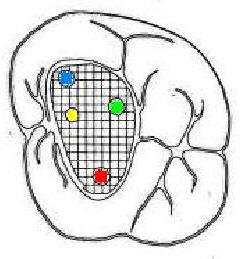

Segundo Molar superior

Presenta tres raíces: dos vestibulares y una palatina y a diferencia del primer molar superior estas no están tan separadas. Además, es frecuente encontrar fusionadas una de las raíces vestibulares con la palatina o ambas raíces vestibulares, formando una única raíz y conteniendo un solo conducto. Esta pieza dentaria puede presentar de tres a cuatro conductos y en raras oportunidades dos o uno.